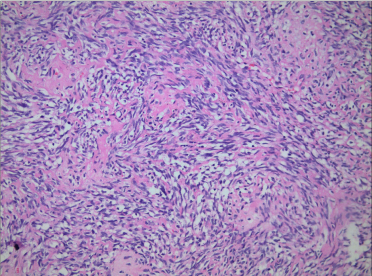

Thus the patient received the surgery. Grossly, the resected mass was a 3.0-cm bone defect of the right mandible (Figure 1). Microscopic examination of hematoxylin-eosin slides showed a neoplasm composed of the epithelial and malignant mesenchymal components. There were large ameloblastic epithelial islands with stellate reticulum-like areas (Figure 2). The mesenchymal component were also composed of large pleomorphic cells and nuclei, hyperchromatic nuclei, and atypical mitotic figures. Some amount of dentinoid material was found in the sarcomatous area composed of spindle cells (Figure 3). Immunohistochemically, amelo-blastic epithelium showed positive for pan Cytokeratin but negative immunoreactivity for SMA and Desmin protein. Malignant spindle cells were weakly positive for SMA but negative for pan Cytokeratin and Desmin protein. The Ki-67 labeling index was higher in the mesenchymal component compared with that in the epithelial component. The post-surgical course of the patient was uneventful.

Figure 3. Some amount of dentinoid material was found in the sarcomatous area composed of spindle cells (HE×400).

The diagnosis of AFDS/AFOS is made microscopically [2,6]. The presented case not only exhibited large areas of ameloblastic epithelium, and also contained the mesenchymal component showing increased cellularity with a sarcomatoid nature in isolated areas. The highly malignant cellular mesenchymal component with marked pleomorphism is essential for establishing diagnosis. There were also small areas with deposition of dentine material adjacent to spindle-shaped cells in the mesenchymal tissue. The combination of these features was the key to the diagnosis.